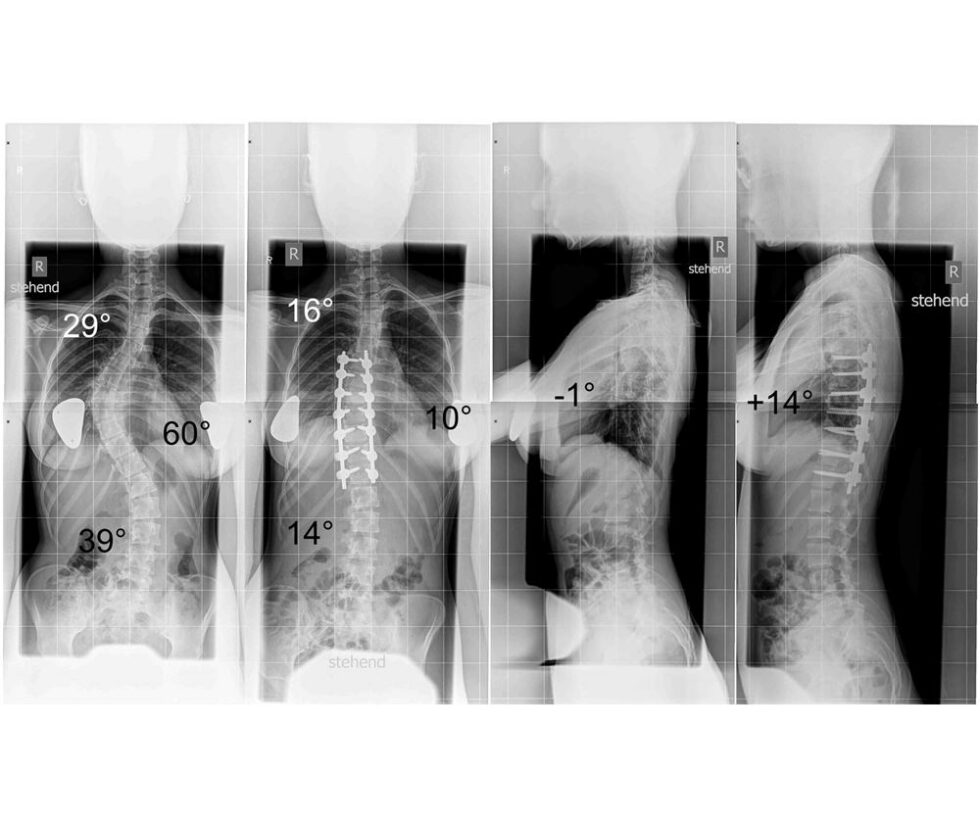

**Hintergrund:** Die Skoliose ist eine dreidimensionale Achsabweichung der Wirbelsäule. Für die Diagnose maßgebend ist eine Krümmung der Wirbelsäule in der Frontalebene von mindestens

Diesen Aufnahmen helfen dem Arzt mehr über mögliche Ursachen, das Ausmaß und die Form der Skoliose herauszufinden. Sollte eine Therapie mit dem Korsett oder eine

Zur weiterführenden Diagnostik gehört das Röntgen. Das Röntgenbild ermöglicht eine genaue Bestimmung des Ausmaßes der Verkrümmung. Aufgrund des Neigungswinkels wird die

Diagnose: Neben der ausführlichen Befragung und körperlichen Untersuchung sichert ein Röntgenbild die Diagnose. Verlauf: Mit frühzeitiger Diagnose und konsequenter Behandlung sind Prognose und Verlauf meist gut.